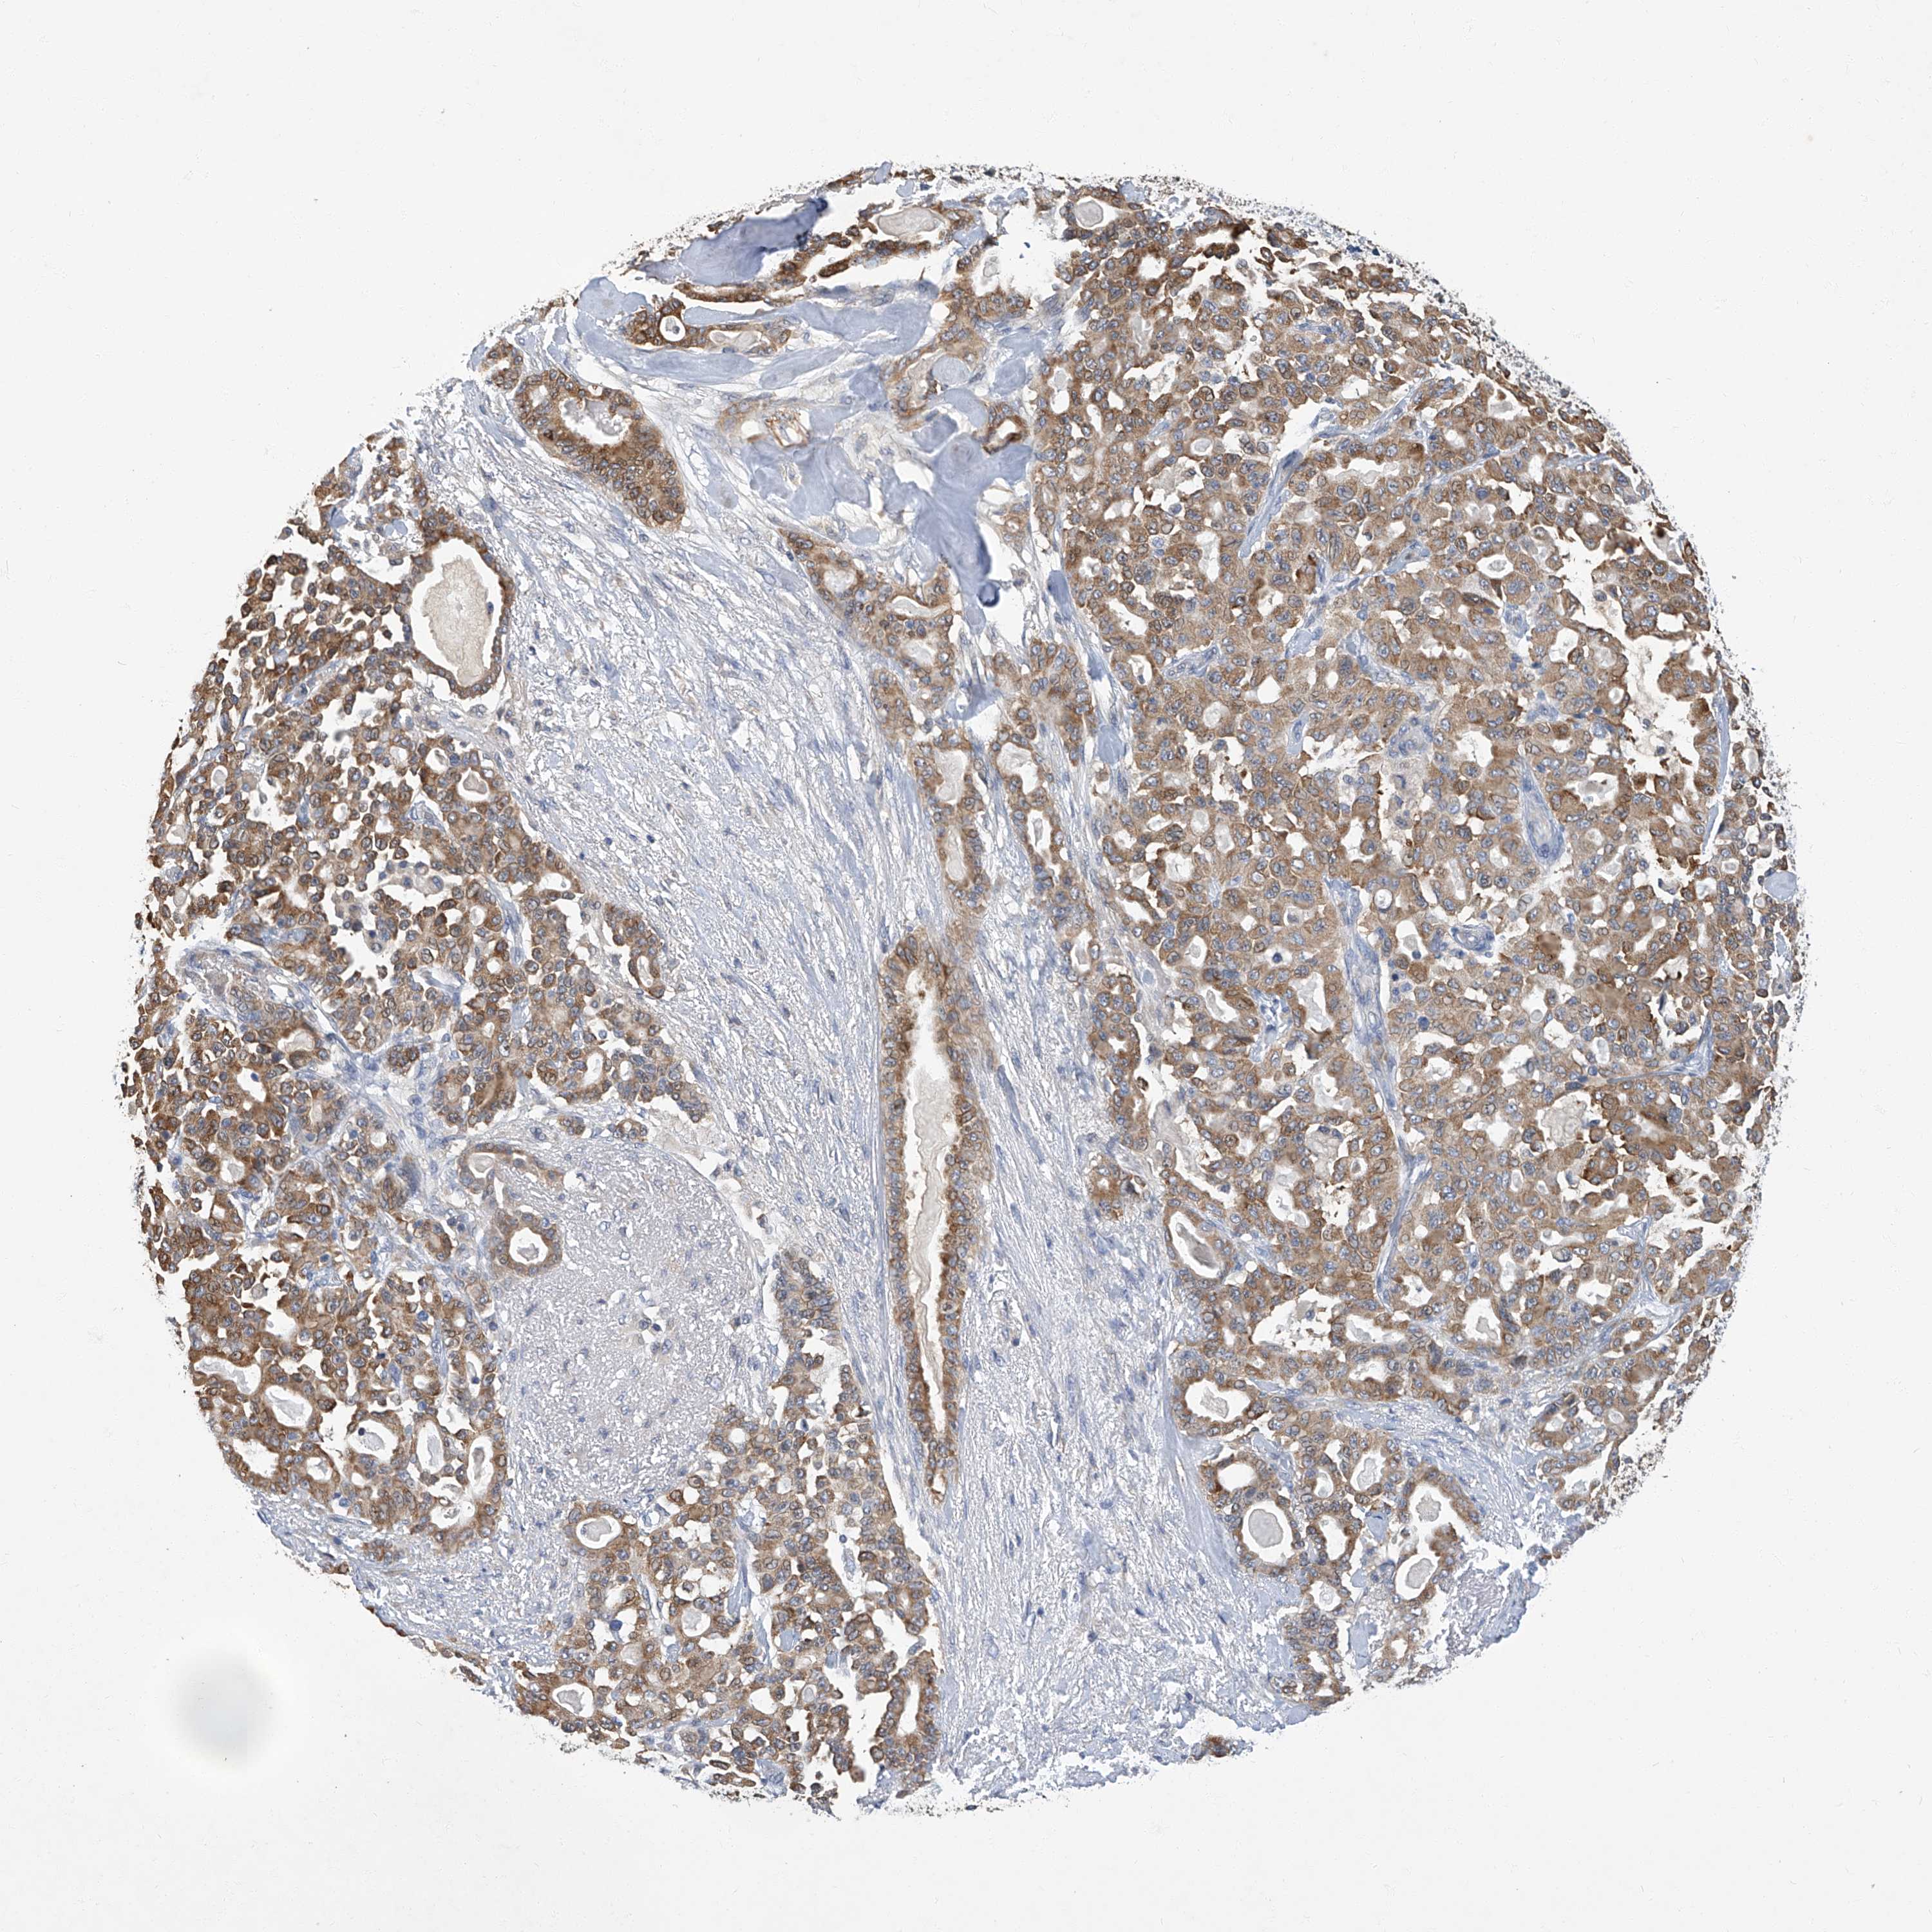

PANCREATIC CANCER - Protein expressioni

A mouse-over function shows sample information and annotation data. Click on an image to view it in a full screen mode. Samples can be filtered based on level of antibody staining by selecting one or several of the following categories: high, medium, low and not detected. The assay and annotation is described here.

Note that samples used for immunohistochemistry by the Human Protein Atlas do not correspond to samples in the TCGA dataset.

Antibody stainingi

Antibody staining in the annotated cell types in the current human tissue is reported as not detected, low, medium, or high, based on conventional immunohistochemistry profiling in selected tissues. This score is based on the combination of the staining intensity and fraction of stained cells.

Each image is clickable and will lead to virtual microscopy that enables deeper exploration of all samples and also displays staining intensity scores, fraction scores and subcellular localization as well as patient and tissue information for each sample.

Antibody CAB002441

Antibody CAB031481

Staining

High

Medium

Low

Not detected

Intensity

Strong

Moderate

Weak

Negative

Quantity

>75%

75%-25%

<25%

None

Location

Nuclear

Cytoplasmic/membranous

Cytoplasmic/membranous,nuclear

Adenocarcinoma, NOS

Adenocarcinoma, metastatic, NOS